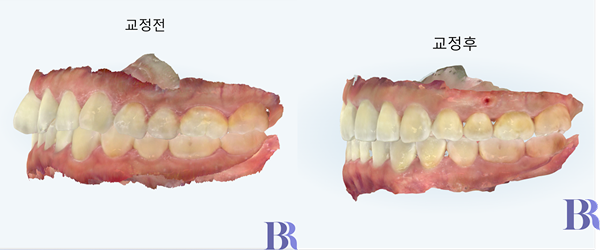

치료 전후 윗니모습

치아 배열이 잘 되었네요.

여기서 잘 되었다는 것은

치아가 뻗지 않고

원래의 아치 속에 첫번쨰

앞니가 잘 들어왔다는 점을

의미하는 것입니다.

아래 치아의 모습인데,

치아의 배열도 좋아졌고

치석 및 치태 등을 관리하기도

훨씬 좋아졌습니다.